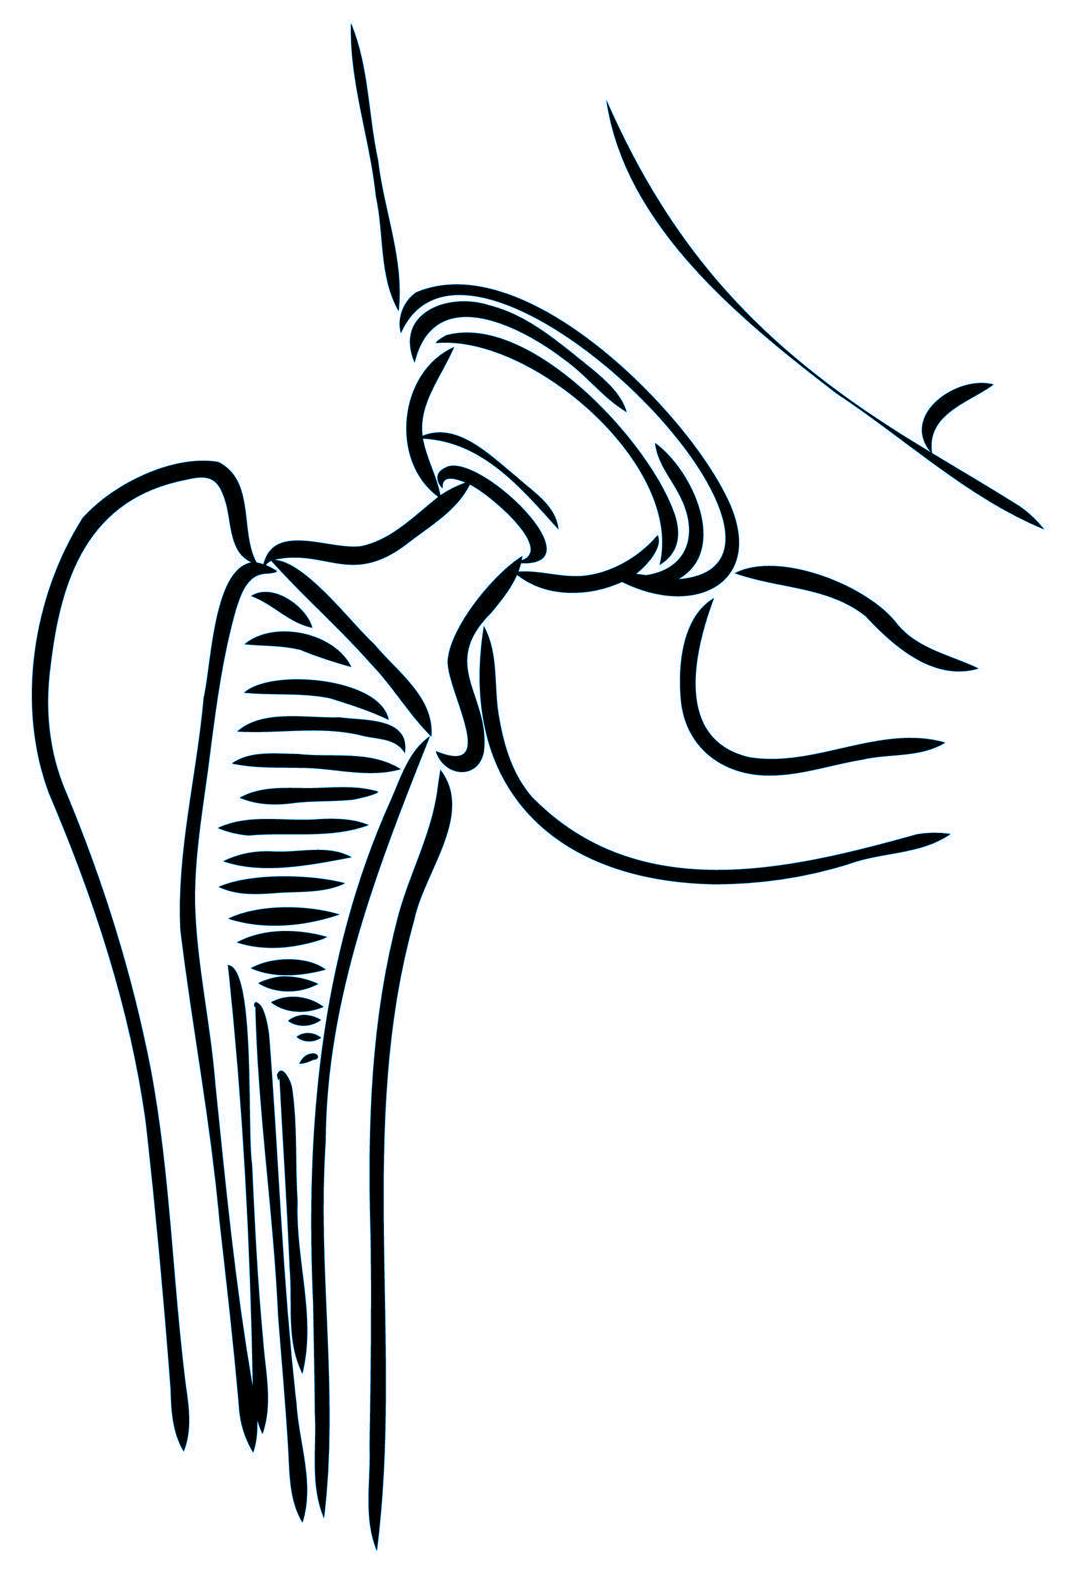

Reemplazo de cadera

Cirugías de Cadera